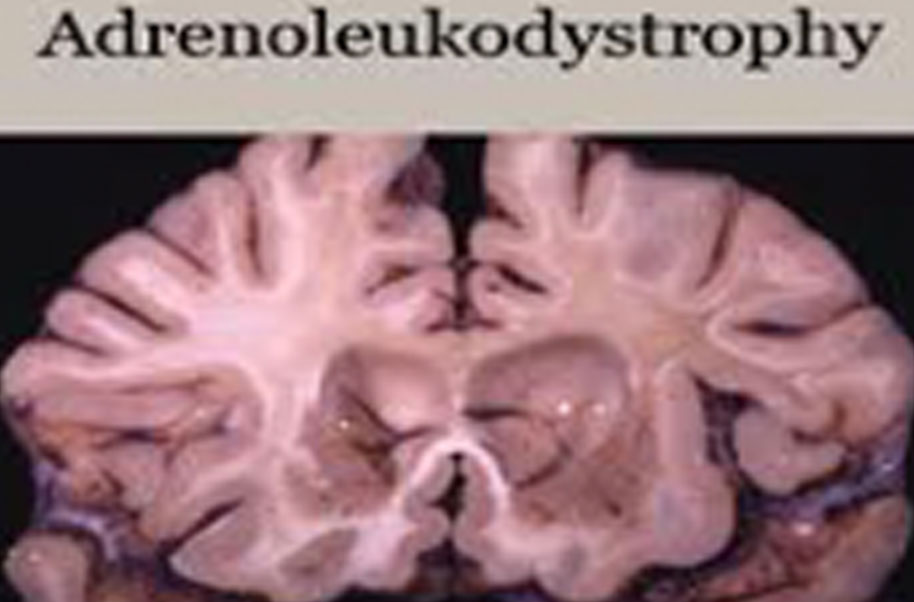

Addison Disease With Cerebral Sclerosis

Ald is one of a group of genetic disorders called the leukodystrophies that cause damage to the myelin sheath of the nerve fibers in the brain. The myelin sheath is a fatty covering which acts as an electrical insulator and there are three types of ald.